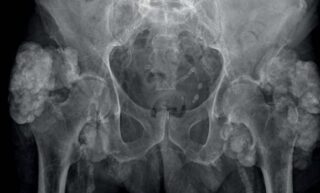

- X-quang khớp háng (Trẻ > 4 tháng tuổi): Sau 4 tháng tuổi, chỏm xương đùi bắt đầu có quá trình cốt hóa (hình thành xương), do đó có thể nhìn thấy rõ trên phim X-quang. X-quang khớp háng giúp phát hiện vị trí của chỏm xương đùi, thường nằm lệch lên trên và ra ngoài so với vị trí bình thường. Một số dấu chỉ điểm quan trọng được sử dụng để đánh giá trên phim X-quang bao gồm:

- Đường Hilgenreiner: Là một đường thẳng nằm ngang, được vẽ đi qua hai điểm thấp nhất của xương chậu (đáy ổ cối) ở hai bên. Bình thường, chỏm xương đùi sẽ nằm ở dưới đường này.

- Đường Perkin/Ombredanne: Là một đường thẳng đứng, vuông góc với đường Hilgenreiner và đi qua điểm ngoài cùng của ổ cối. Bình thường, chỏm xương đùi sẽ nằm ở phía trong đường này.

- Chỉ số góc ổ cối (Acetabular Index): Góc ổ cối được đo giữa đường Hilgenreiner và một đường kẻ từ điểm thấp nhất đến điểm ngoài cùng của ổ cối. Giá trị trung bình của góc này là khoảng 27.5 độ ở trẻ sơ sinh và giảm xuống khoảng 23.5 độ ở trẻ 6 tháng tuổi. Trong trường hợp loạn sản khớp háng, góc này thường mở lớn hơn 30 độ.

- Cung bịt (Đường Shenton): Là một đường cong ảo được tạo bởi bờ trong của cổ xương đùi và bờ dưới của xương mu. Bình thường, đường này liên tục và trơn tru. Trong trường hợp trật khớp háng, đường Shenton sẽ bị gián đoạn.